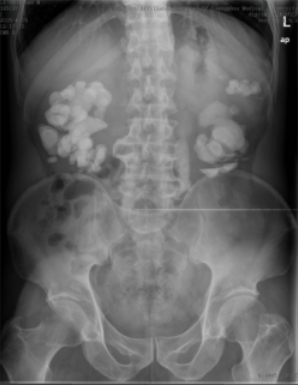

看一看这疯狂的石头,几乎把双肾有的空间都占满了,特别是右肾(图片左侧)。而这石头的拥有者——患者李先生和家属四处投医无果后,最后慕名来到泌尿外科就诊。泌尿外科专家经过一番研究讨论后,决定先使用经皮肾镜行左侧经皮肾碎石取石术,为左边肾脏进行结石清除。术后,再次为李先生进行x光检查,结果显示:左边结石已基本清除。